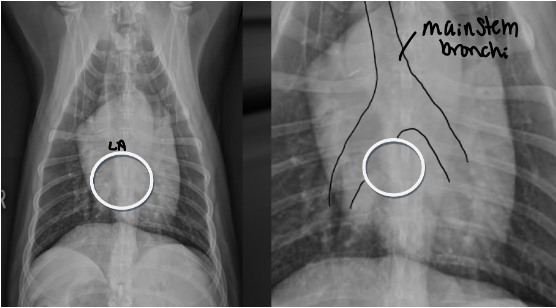

Where does the left atrium sit on the clock face

Located between main stem bronchi which straddle it like a cowboy

3 features of LAE on DV

-double opacity sign

-separation of main stem bronchi

-LA bulge at 2:30-3 o’clock

What part of the heart is enlarged

LAE